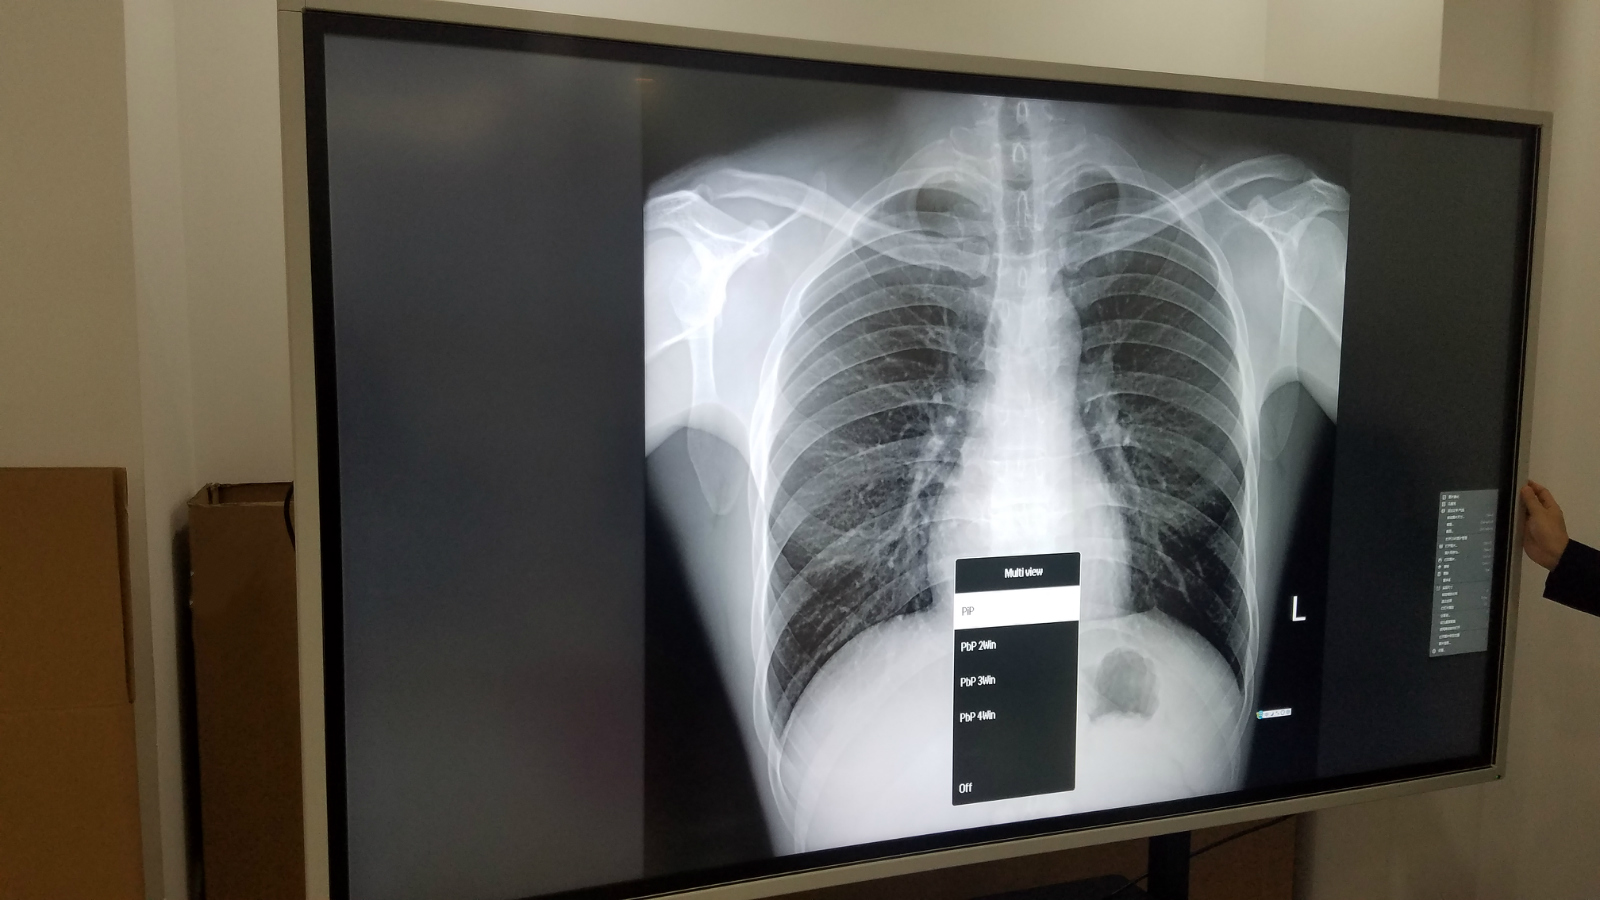

德恪商用本着“德行天下,恪尽职守,持续为客户创造最大价值”的理念,针对医院会诊,远程医疗,跨区域诊断,手术综合应用,医疗教学等应用场景而设计推出专业会诊大屏,尺寸涵盖:65寸,75寸,86寸,98寸,完全符合Dicom标准,满足医疗影像稳定一致的显示需求;具有超高分辨率、稳定亮度、忠实色彩还原、使用寿命长的优点; 支持一屏多显,可链接医院多种系统(如PACS、HIS系统),满足医院多种诊断及手术作业等需求。

小编这就带大家去看看DEKCO品牌98寸会诊大屏工艺展示实物拍摄效果:

德恪DEKCO会诊大屏无论是从功能实现上还是对灰阶显示参数指标,甚至信号接口,相较于商用显示器而已,无疑是提出了更高的要求,德恪商用由最初的“液晶显示系统解决方案提供商”的定位,现今添加了“医疗影像显示系统解决方案提供商”,给用户提供更优质,高品质的医疗会诊大屏解决方案。